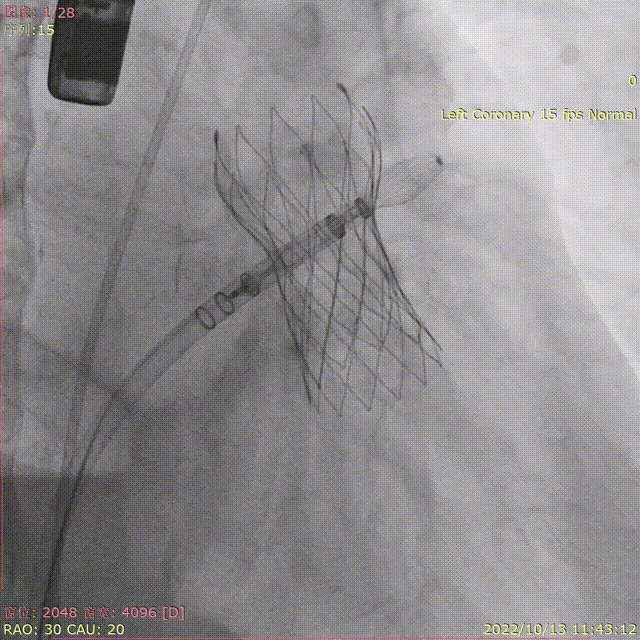

瓣膜释放

完全释放后造影